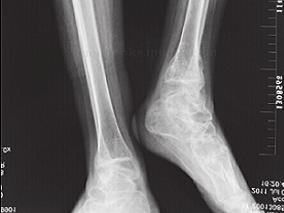

男13岁,多发骨折4年

环球医学资讯

2016年09月07日

点击量:397

1小时条评论患者男性,13岁,于2011年7月5日入院。 一、主诉 多发骨折4年。 二、病史询问 (一)诊断思路及问诊目的 患者青少年男性,反复多次骨折,考虑到代谢性骨病如先天性成骨发育不全、骨质疏松症、骨软化症、佝偻病的可能。 此患者年轻,需重点考虑先天性成骨发育不...